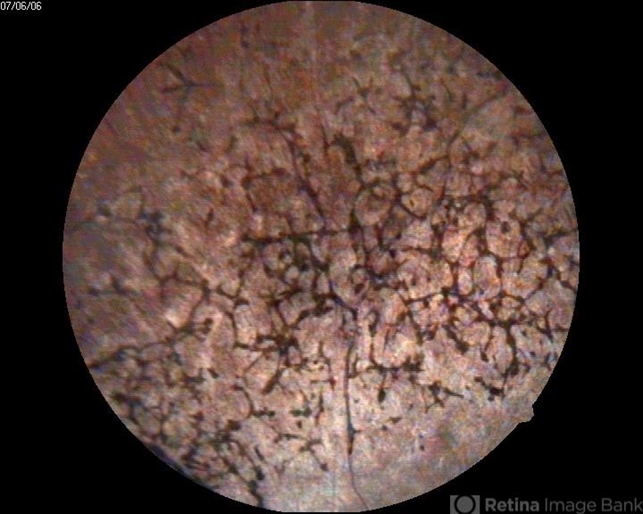

- retinitis pigmentosa (RP) dystrophy

- A 42-year-old female presented with gradual reduction in vision.